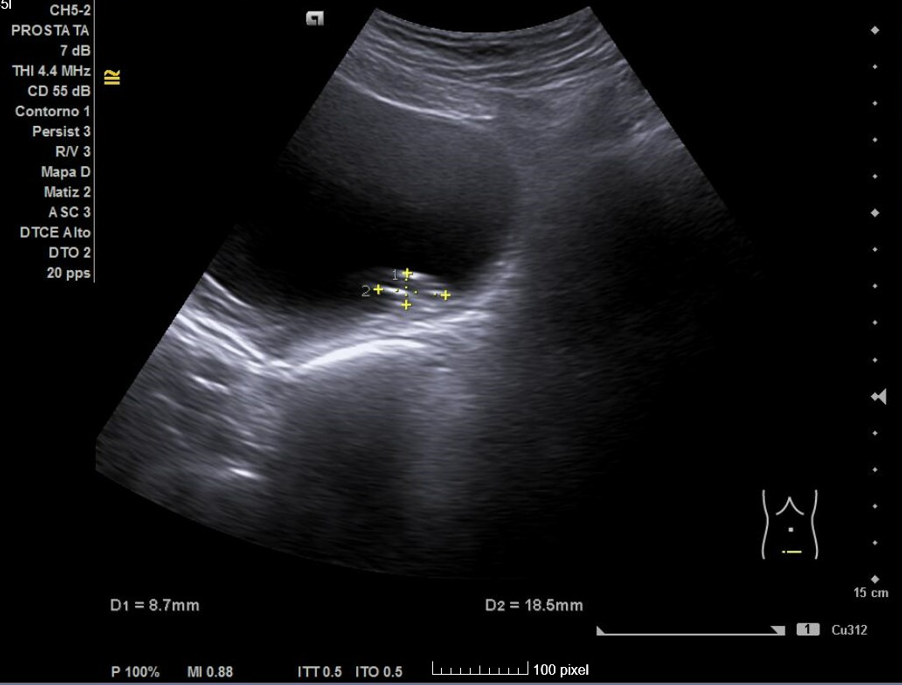

Primera ecografía: Riñón derecho de 9,6 cm, izquierdo de 9,5 cm, escoestructura y morfología normales. Vejiga con aumento de grosor de pared, residuo premiccional y posmiccional similares en torno a 350 cc (probable vejiga de lucha). Pólipo vesical a expensas de pared inferior izquierda de 18,5 x 8,7 mm. Jet ureteral bilateral conservado. Próstata de 110 cc. Se repite ecografía al mes: Pólipo vesical de 14 x 9,7 mm, próstata de 119 cc, vejiga con volumen premiccional 469 ml y posmiccional 400 ml.